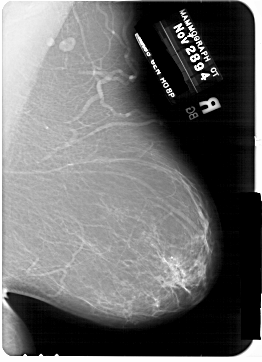

A_1769_1.RIGHT_CC

RIGHT_CC LINES 6871 PIXELS_PER_LINE 4621 BITS_PER_PIXEL 12 RESOLUTION 43.5 NON_OVERLAY